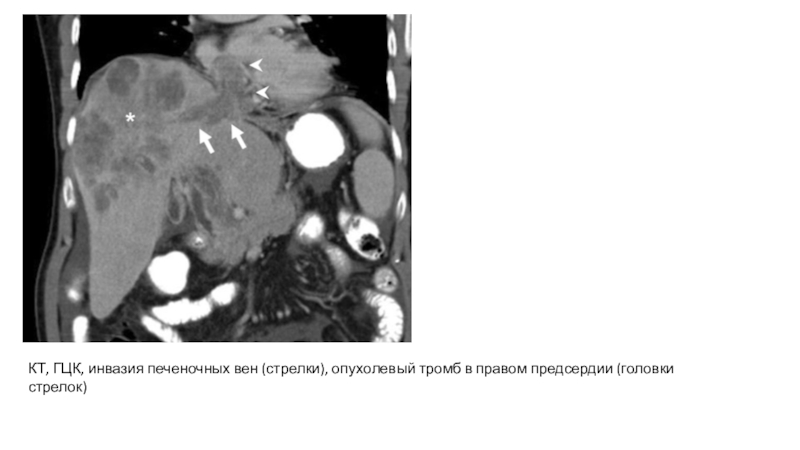

Слайд 21КТ, ГЦК, инвазия печеночных вен (стрелки), опухолевый тромб в правом

предсердии (головки стрелок)

КТ, ГЦК, инвазия печеночных вен (стрелки), опухолевый тромб в правом предсердии (головки стрелок)